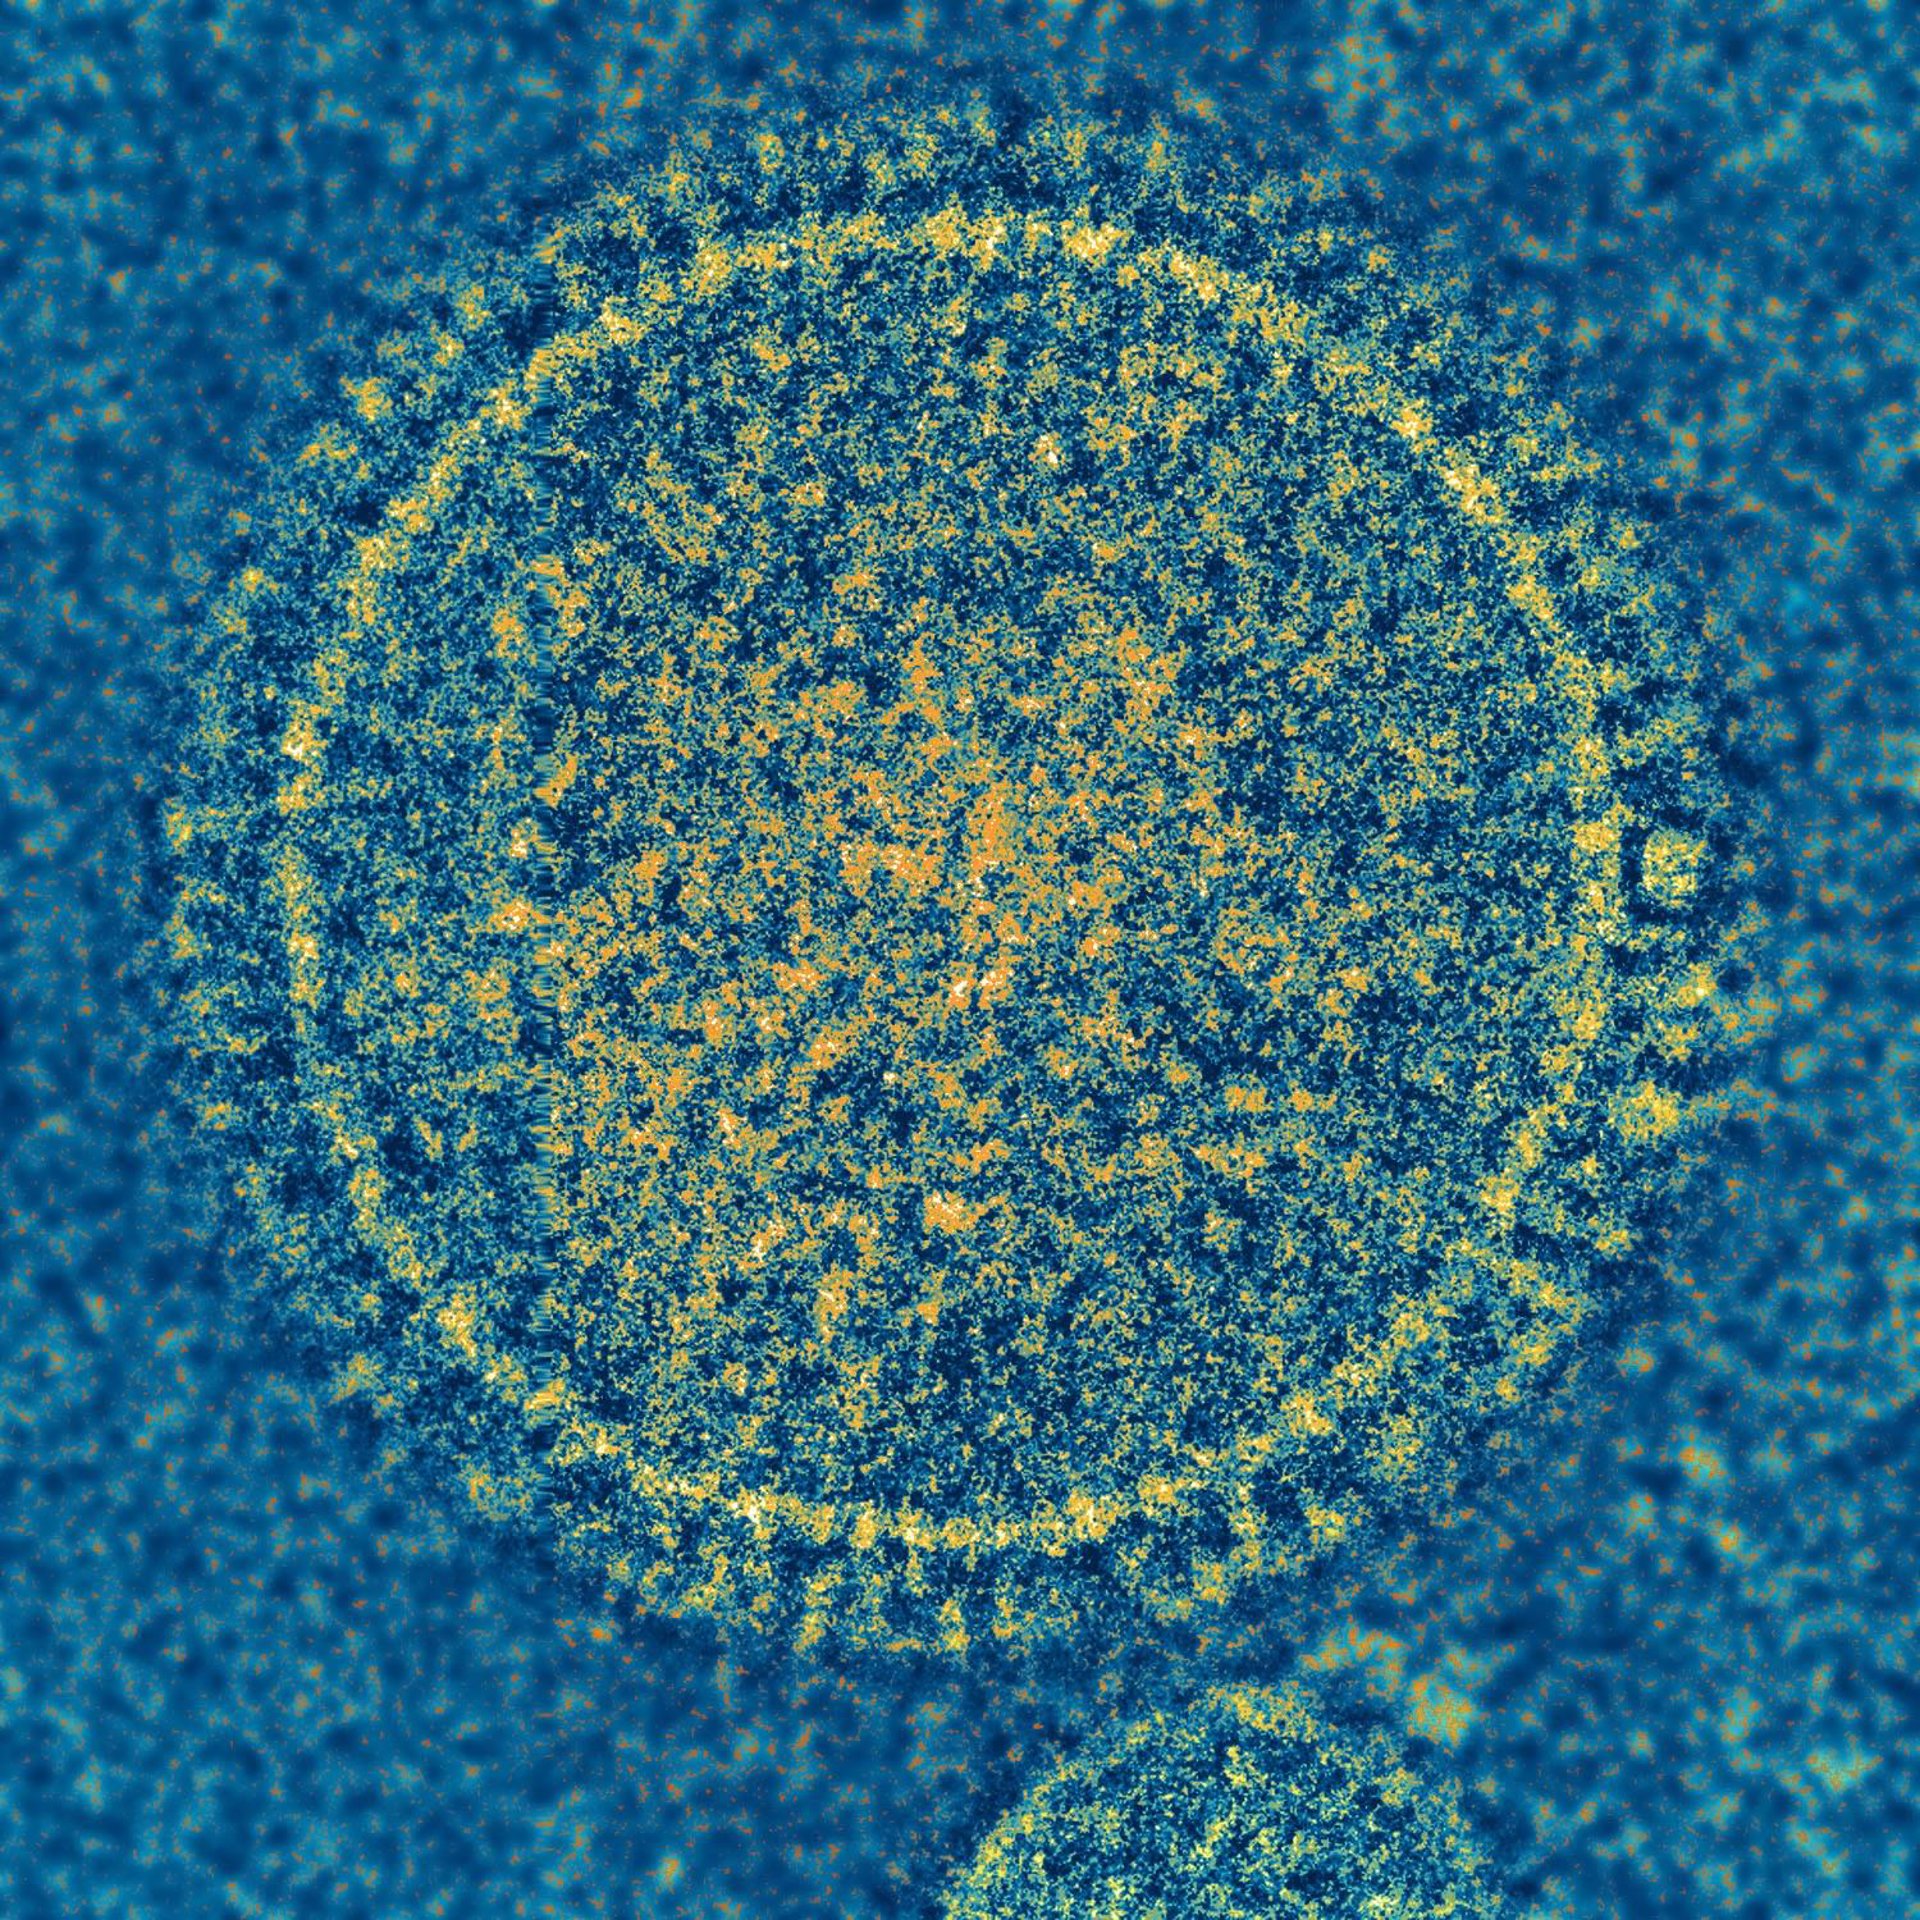

El virus sincitial respiratorio (VSR) es el responsable de una enfermedad común de la infancia. No hay vacuna para prevenir la infección por VRS.

El virus sincitial respiratorio (VSR) es el responsable de una enfermedad común de la infancia. No hay vacuna para prevenir la infección por VRS. - NIAID - Archivo

El VSR es una enfermedad común en niños y representa la causa más frecuente de hospitalización en recién nacidos en los países desarrollados, aunque a menudo solo causa síntomas leves.